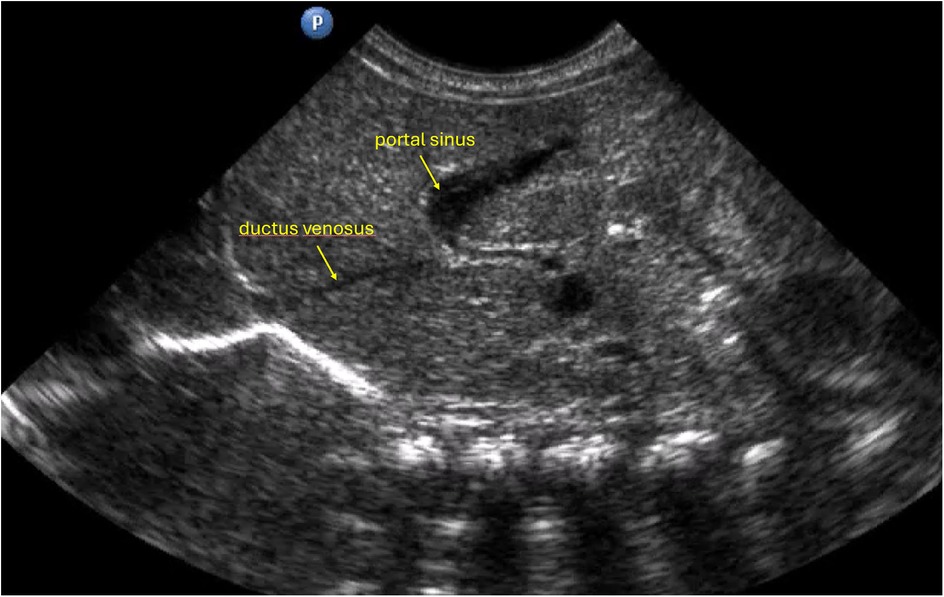

Figure 1

Ultrasound image displaying the liver of the newborn. Labeled structures include the ductus venosus, portal sinus, and umbilical vein. The labels are in yellow, with arrows pointing to each respective structure.

Figure 1. Anatomical configuration characterized by a relatively wider angle between the ductus venosus and the left portal vein, together with a relatively wide ductus venosus lumen, which may facilitate smoother advancement of the catheter during insertion.